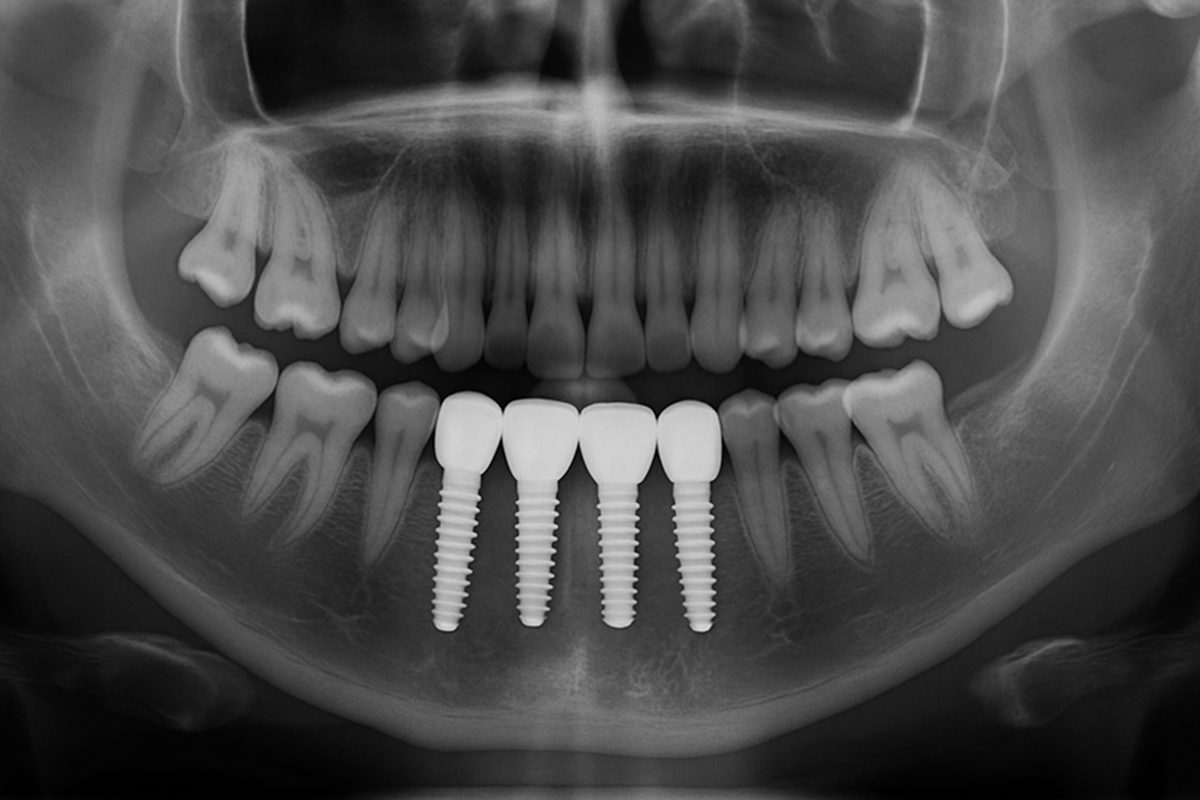

A dental implant post is the part that goes into the jawbone and acts like a tooth root. The implant restoration has three basic parts: the post (fixture or implant body), the abutment (connects the post to the crown), and the crown (the visible tooth). The post provides stability so the abutment and crown function like a natural tooth.

One-piece vs two-piece implant systems

One‑piece implants combine post and abutment into a single unit. Two‑piece systems separate the post and abutment, offering more flexibility for angulation and restorations. Choice depends on location, bone shape, and the clinician’s plan.

Placement begins with evaluation and imaging to assess bone and nerves. Planning may include digital scans and surgical guides. Surgery places the post into bone; sometimes a bone graft or sinus lift is needed first. Then healing and osseointegration take weeks to months. After stable integration, the abutment and crown are attached. Typical healing is 3–6 months, shorter with immediate-load protocols in select cases.